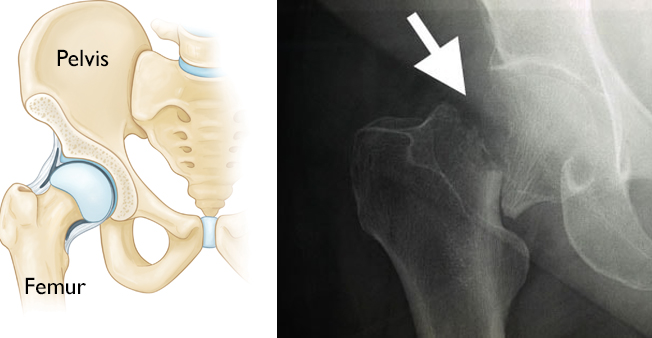

Illustration of a normal hip and x-ray of a hip fracture

Hip fractures occur in the upper section of the femur (thighbone). The X-ray image on the right shows a hip fracture.